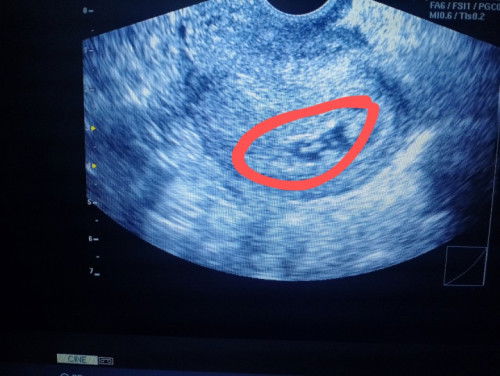

Unclear/Foggy Gestational Sac

First time mom, age of 23. Ask ko lang po if may naka experience po ng foggy results of ultrasound dito. Yung sakin po kasi foggy po yung pinaka loob ng sac unlike sa iba na clear black po yung sac. Although nakita si baby and unsure po kasi ako sa exact last mens ko but I did took the PT last May 29. Napapaisip po ko baka early lang masyado or technical lng problema. Nag-aalala po ko kay baby. 🙁 Tyia!